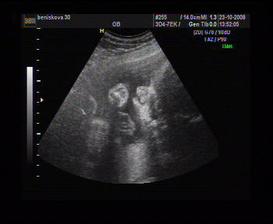

29.5. mi paní doktorka potvrdila, co už jsme samozřejmě dávno věděli a ukázala mi naše embryjko na ultrazvuku, kde mu krásně tikalo srdíčko a mělo celých 1,11 cm...no prostě jednička. Bylo to krásný 🙂

12.6. proběhnul další ultrazvuk, tentokrát to nastávající mamča pěkně obrečela a do toho se s paní doktorkou smála, co tam ten sněhuláček dělal za alotria 🙂) A máme už průkazku! 🙂

23.7. první 3D ultrazvuk (v 15+3) - jedním slovem úžasný!!! 🙂

28.8. (20+3) 3D UTZ i s nastávajícím tatínkem, bylo to super, miminko předvádělo prostocviky a ukázalo nám, že rtíky i patro má v pořádku (maminčiny obavy kvůli rod. anamnéze). Hurá! 🙂)

25.9. kontola u paní doktorky, sice mamka pořád nepřibírá, ale malej lumpík je úplně v pořádku, koukaly jsme na něj na 3D UTZ a bylo to prima 🙂